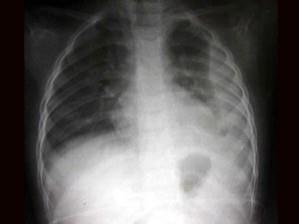

问题 男2岁,左侧胸痛、气促,如图所示,最可能的诊断为?(?)

选项 A.左肺肺不张 B.左侧胸腔积液 C.左侧胸膜肥厚 D.右肺肺气肿 E.以上都不正确

答案 B